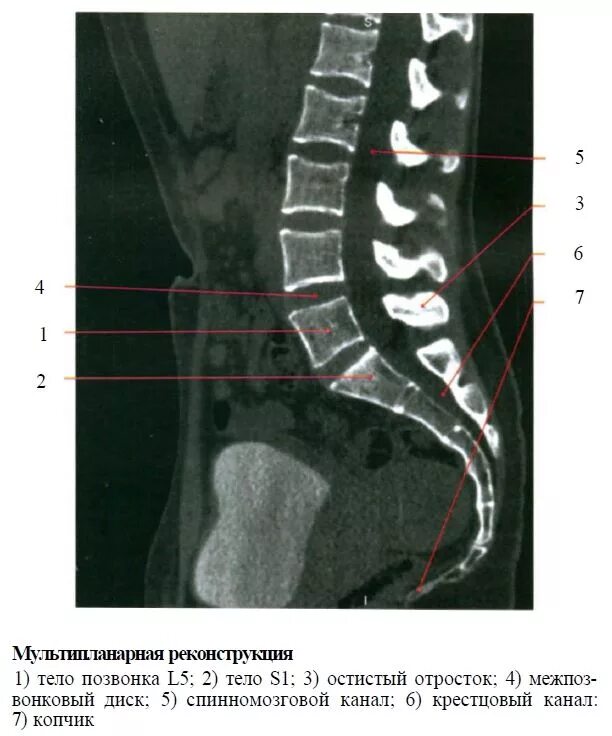

Пояснично крестцово копчиковый отдел